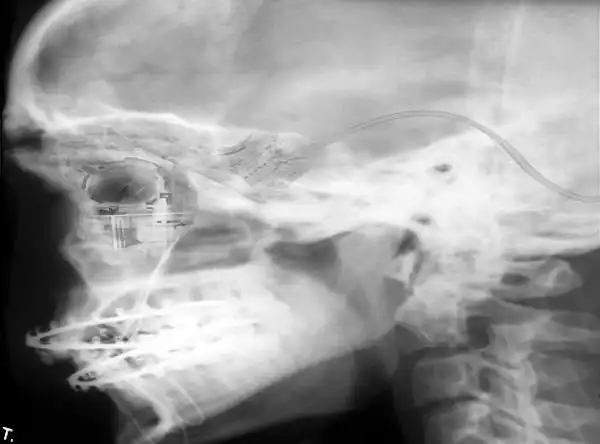

5

Рентген лица со встроенным чипом от компьютерной мышки.